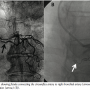

Case Report. A 62-year-old man was admitted with angina on moderate exertion and dyspnea. He had a history of hypertension, diabetes, and smoking and was on aspirin, atenolol, glibenclamide, and alpha-methyldopa. Due to pulmonary symptoms, we performed chest computed tomography (CT), bronchoscopy, and lung biopsy, which revealed bronchiectasis, interstitial fibrosis, and chronic bronchitis in the right lung. During the investigation echocardiography showed left ventricular diastolic dysfunction grade 1, ejection fraction of 65%, and mild mitral regurgitation. Exercise testing revealed ST segment depression of 1.5 mm and typical chest pain in the fourth minute of Bruce protocol. No significant changes were shown during 99mTc-sestamibi scintigraphy. Coronary CT did not reveal any coronary luminal reduction. Nevertheless, it demonstrated a retro-aortic connection between the coronary artery and

the pulmonary vasculature (Figure 1). Therefore, we performed coronary angiography, which depicted no coronary artery disease. However, it identified a fistula between the circumflex artery and right bronchial artery (Figure 2A). The fistula was successfully occluded at its proximal third with 3 coils (3 mm/3.3 mm + 4 mm/3.7 mm+ 5 mm/5.5 mm) (Figure 2B). The patient remained stable, with normal ECG and cardiac enzymes after 48 hours. At 1-month follow-up, the patient continued with the same complaint of angina. A new coronary angiography was performed. It showed no stenosis or induced coronary spasm and total occlusion of the fistula at its proximal third.